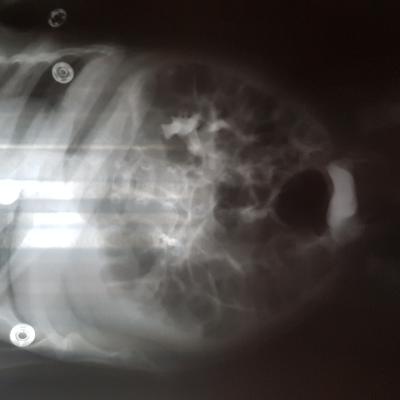

Добрый день! Еще внутриутробно у ребенка обнаружили расширение лоханок.Провели обследование в 1.5 месяца.Поставили диагноз болезнь Ормонда.И назначили консервативное лечение.В 2ух мочеточниках по несколько наростов.рефлюкса не было.Скажиье, возмлжнл что ребенок поосто перерастет?

Болезнь Ормонда (ретроперитонеальный фиброз, забрюшинный фиброз) – хроническое воспаление жировой клетчатки забрюшинного пространства, которое постепенно приводит к компрессии и нарушению проходимости трубчатых структур данного анатомического участка. Чаще всего, в качестве этих тубулярных структур выступают мочеточники.

У меня есть сомнения, что причиной гидронефроза в Вашем случае явилось именно это состояние.

Возможно речь идет о пузырно-мочеточниковом рефлюксе.